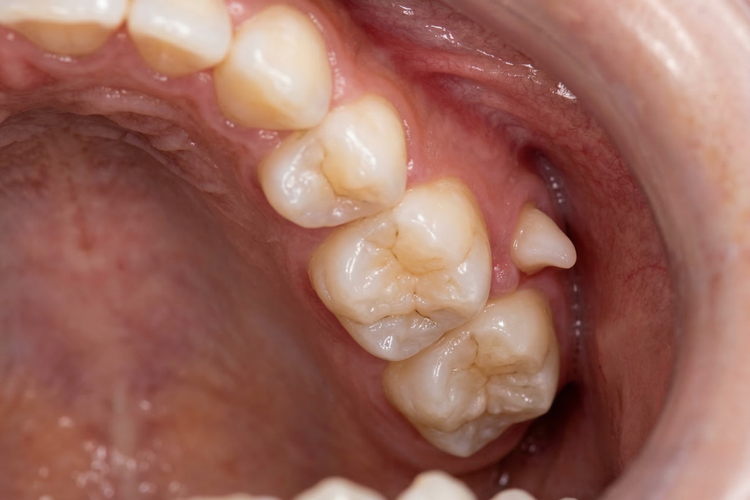

Intraoral photograph showing the upper dental arch with an extra molar.

Intraoral view showing a paramolar supernumerary tooth beside the molars.

Paramolar Develops beside or between the molars at the back of the mouth, usually on the cheek-facing side of the molar teeth.